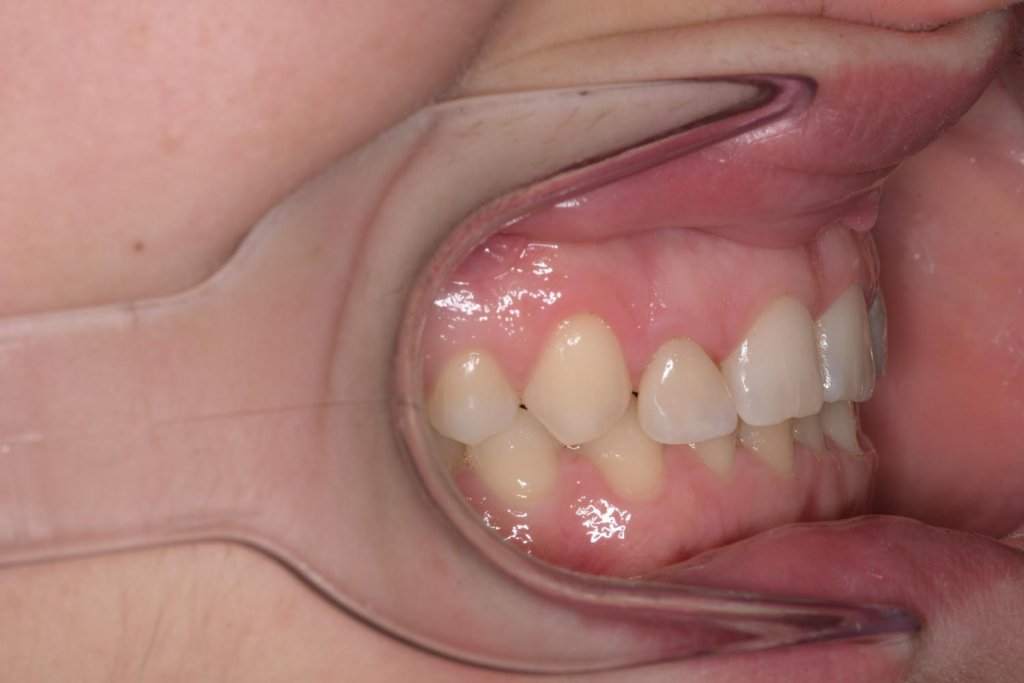

Me cuenta que ya en pasado, a los 18 años, se sometió a una ortodoncia y intentar enmascarar la microdoncia de los laterales con unas «carillas cerámicas». Esto era el resultado de dicho tratamiento:

La paciente rechazaba cualquier tipo de tratamiento ortodontico (por cansancio y porque trabaja cara al publico), tras mucho esfuerzo consigo convencerla a ponerse ortodoncia al menos en la arcada inferior para aprovechar de estos espacios para ganar resalte y corregir la sobre mordida y sobre todo poder generar una guía canina una vez completado el tratamiento restaurador.